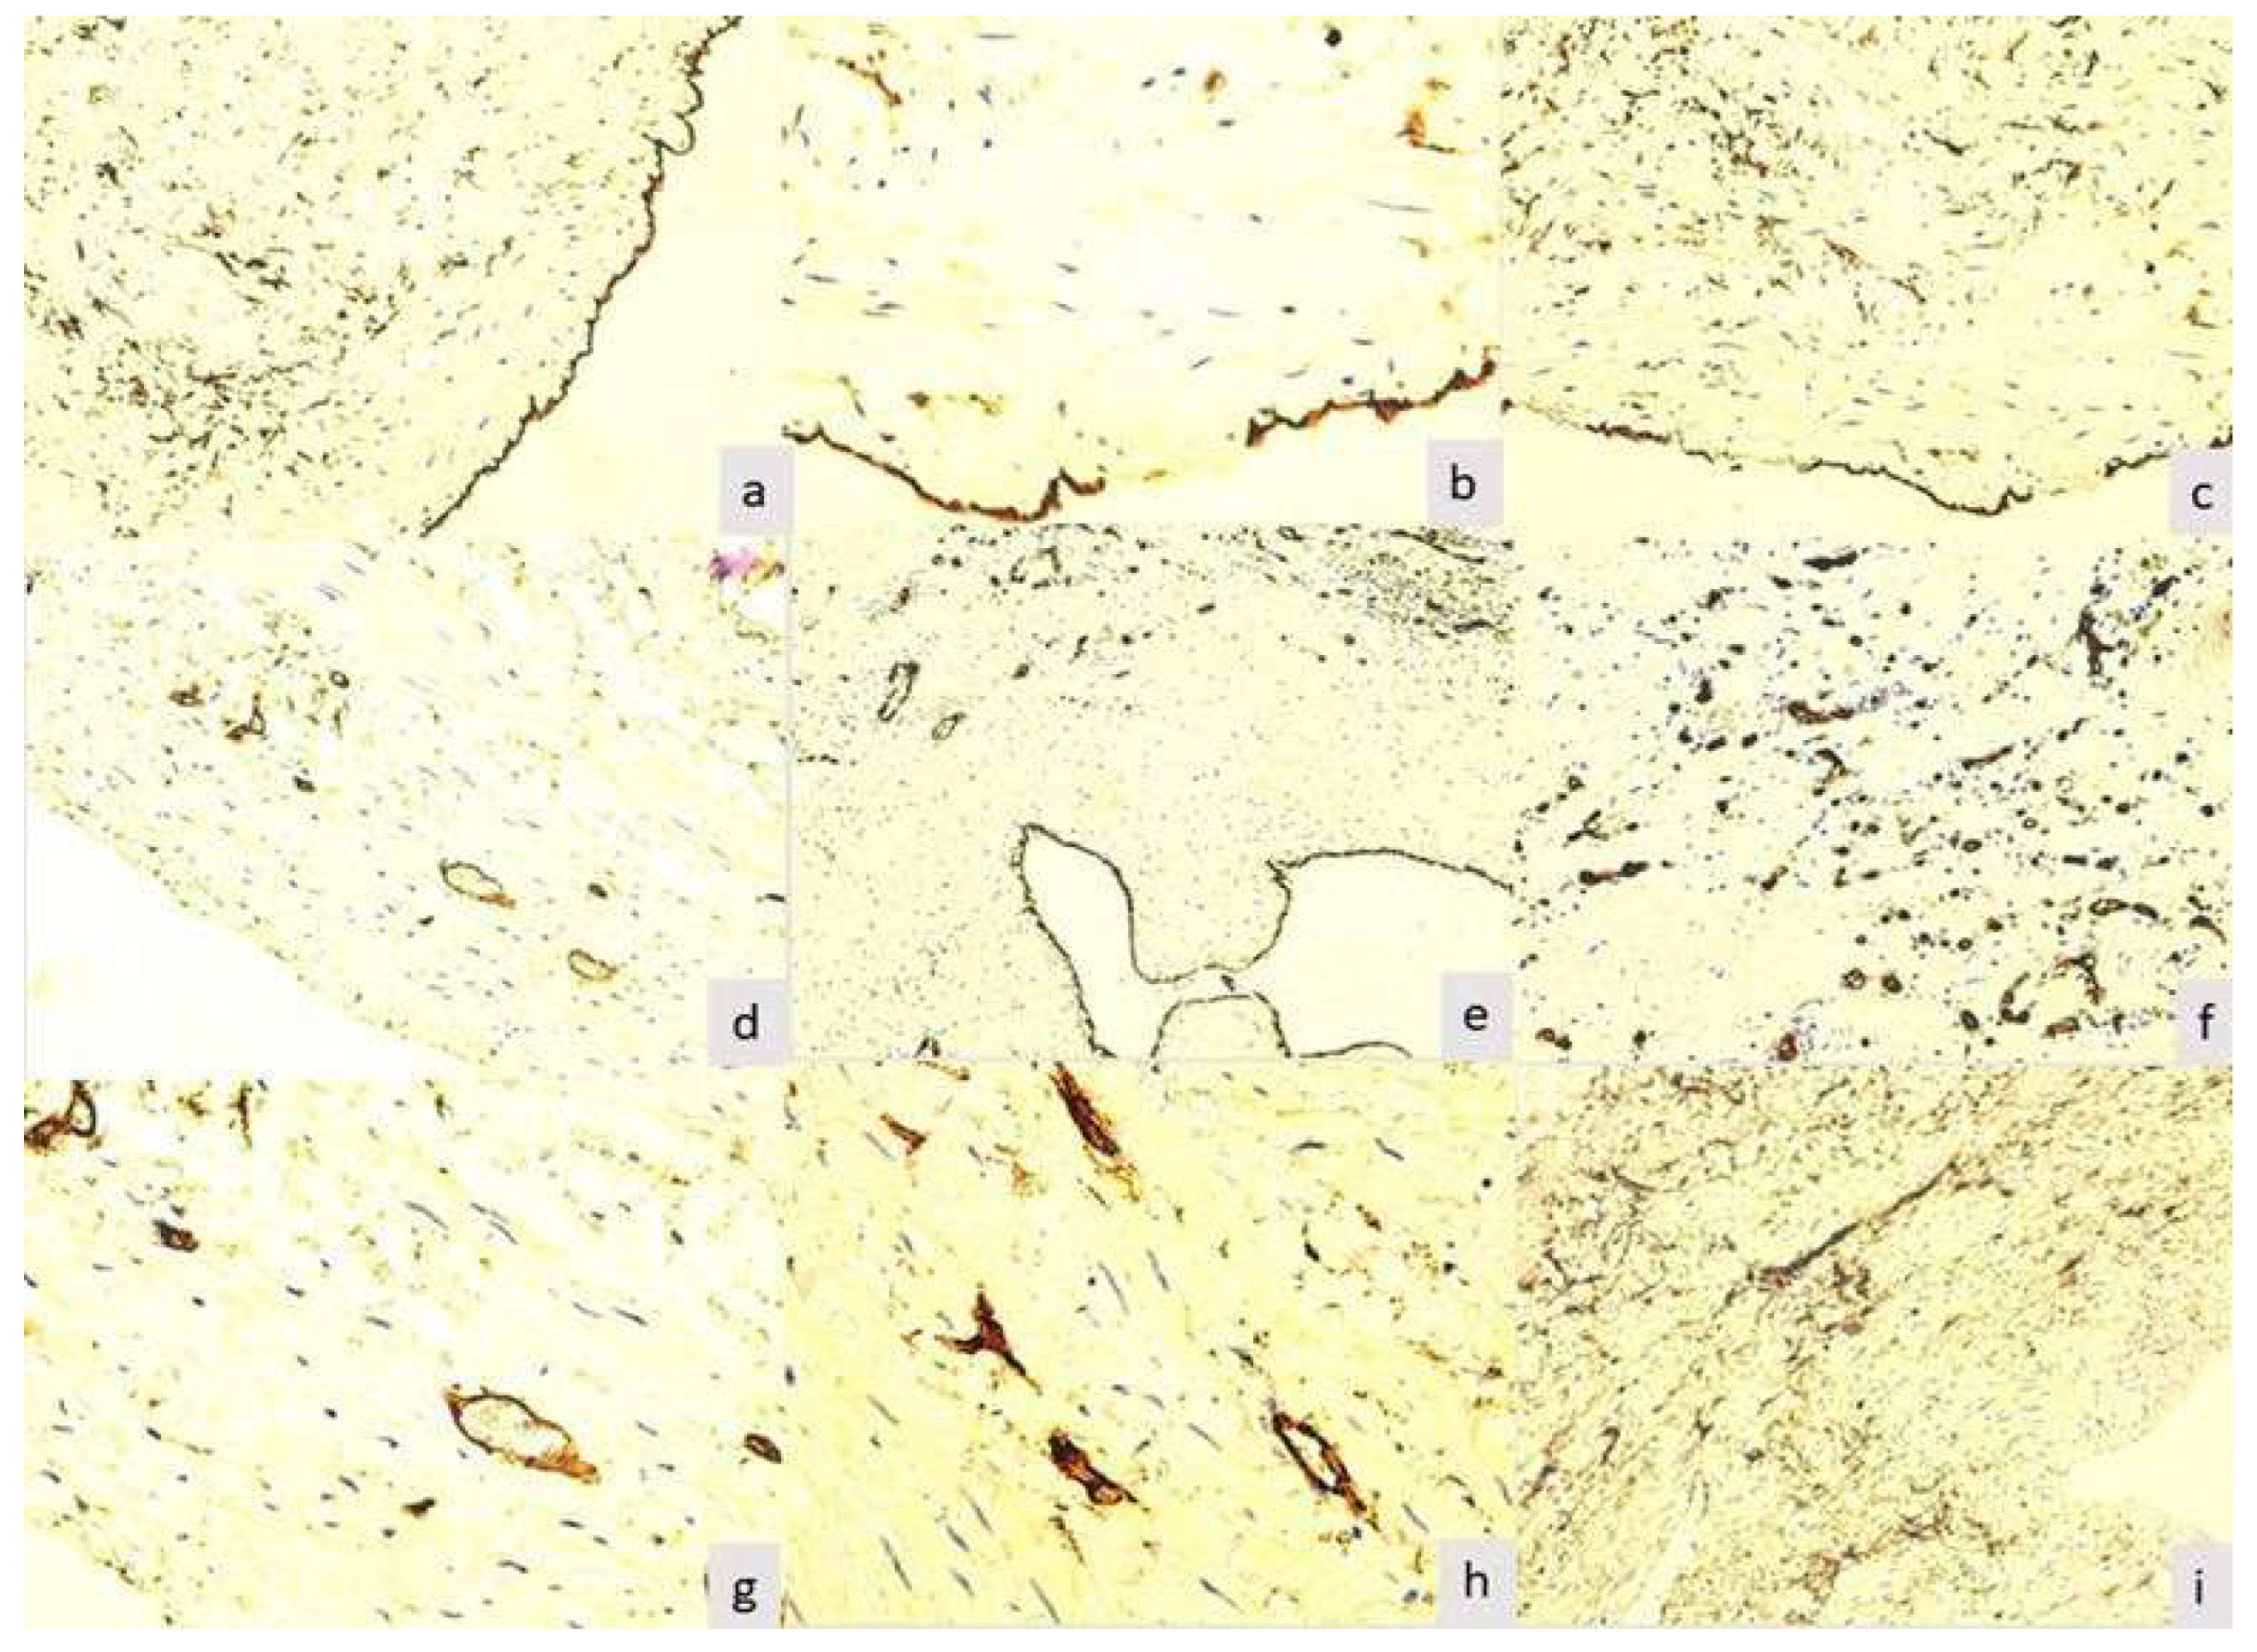

The final product of the immunoreaction for CD34 for zero-hourtimewas located at all three levels of the wall of varicose veins excised by cryostripping. At the level of the intima, the layer of endothelial cells was intensely and homogeneously positive (p=0.001). This aspect was found in 89(81.61%) of the 109 samples studied (Figure 1a).

Between zero-hour time and 12 hours, no major changes were observed in the samples studied, which were also statistically significant (zero-hour time: p-value=0.0021; 2 hours: p-value=0.0136; 4 hours: p-value=0.0348). Changes in all layers appeared after 12 hours (12 hours: p-value=0.0499; 24 hours: p-value= 0.0582), but especially at the intima layer started to be seen after the samples had been in physiological solution for 12 hours, so that at the endothelium level lacunar expressions appeared in 32 (29.35%) cases and at 24 hours multiple lacunar expressions appeared in 53 (48.62%) cases.

After 48 hours in physiological solution, it was noticed a single (Figure 1b) or multiple (Figure 1c) lacunar expression.These aspects underlined damage to the endothelium induced by the surgical procedure used, associated with the duration of preservation of the specimens in physiological serum. Therefore, at the level of the endothelium, 37 (33.94%) specimens were negative for this immunoreaction (Figure 1d). Small blood vessels in the media served as an internal positive control, with positive endothelium. In 97 (88.99%) of the samples studied, the subintimal space did not show positive cells for this reaction.

Three cases were found that showed typical aspects of recanalized thrombus, where some particular aspects were observed. The endothelium of all evaluated lumens was intensely positive for CD34. In its immediate vicinity in the subintimal space, was not observed any other positive cells or small neoformation vessels(Figure 1e).Small vessels, with characteristic morphology for capillaries and postcapillary venules, were present at a relatively large distance from the neointimal space, being included in a tissue dominated by connective cellular elements, with rare fibers and without acute or chronic inflammatory infiltrate.The small vessels in the recanalized thrombi showed thick endothelium with a visible lumen or not (Figure 1f), signaling the presence of neoformation vessels. The density of these vessels was very high per surface unit, coinciding with the proliferation phase of the endothelium. For this reason, these aspects recapitulate some stages of physiological angiogenesis, but we believe that the thrombosed venous vessel model is particularly useful not only for understanding some stages of angiogenesis, but also for testing inhibitory medication on this process.

After 48 hours, in 46 (42.2%) of the 109 samples studied, was observed the normal appearance of the venous media, respectively showing smooth muscle cells and small blood vessels in the middle area (Figure 1g). Some cases showed average blood vessels with one or more buds, suggesting endothelial cell activation (Figure 1h). The vessels in which were noticed aspects of budding did not present visible lumen in optical microscopy, being classified as immature. In the other cases, and especially in those with partial or no endothelium stained for CD34, was found obliteration of the border between media and adventitia. Adventitial cells diffusely and heterogeneously invaded the media, up to the vicinity of the subintimal space (Figure 1i). The adventitial cells show long, elongated cytoplasmic extensions, which tend to be a dense network in the external portion of the media, being in direct continuity with the adventitia. Although the morphology in this technical form is a static investigation, we believe that these aspects suggest the mobilization and migration of adventitial cells towards the other layers of the venous wall, a phenomenon that obviously occurs during the evolution of the venous disease.

Figure 1. CD 34 immunostaining. Venous wall showing intensely and homogeneously stained endothelium (a, x100); Endothelium with segmental positive reaction for CD34 (b, x200); Multiple defects of the endothelium (c, x200); Negative reaction of venous endothelium, positive for medium small vessels (d, x200); Recanalized thrombus. Irregular lumen, with intense positive reaction for CD34 at the level of the endothelium (e, x100); Detail with small vessels in the thrombus reorganization area (f, x400); Vein musculature showing only small blood vessels (g, x200); Blood vessels in the media of the varicose vein with multiple sprouting aspects (h, x200); Media invaded by adventitial cells with dendritic morphology (i, x100).